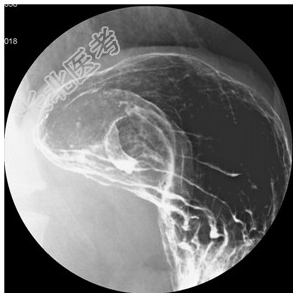

- [材料题] 男性,55岁。反复黑便1月。行X线检查。

- 简答题1、患者的诊断及依据是什么?

- 简答题2、鉴别诊断有哪些?